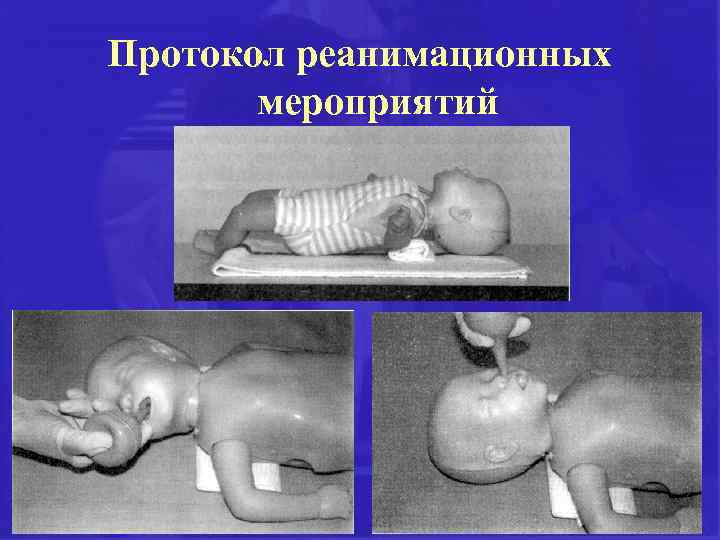

Протокол реанимационных мероприятий при асфиксии

Протокол реанимационных мероприятий при асфиксии

Протокол реанимационных мероприятий при асфиксии

Протокол реанимационных мероприятий при асфиксии